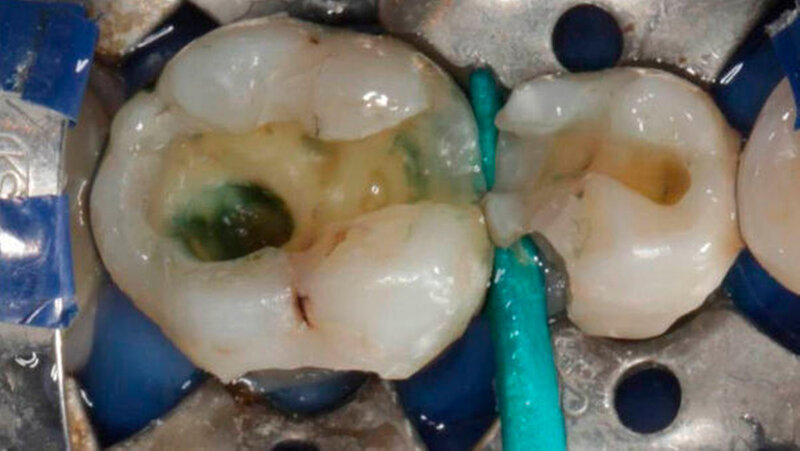

Das Röntgenbild zeigte, dass die Füllungen bei Zahn 45 und 46 nahe an der Pulpakammer lagen. Mit EPT (32/80, 35/80) und thermischen Tests wurde die Pulpavitalität geprüft (normal). Die Diagnose lautete: tiefe Karies. Die Kompositfüllungen wurden daraufhin möglichst substanzschonend ersetzt.

Die Behandlung umfasste zwei Termine (erster: Zahn 46 und 45, zweiter: Zahn 43 und 44). Zur Entfernung der alten Füllungen dienten ein runder und ein zylindrischer Diamantbohrer sowie langsam laufende Hartmetallbohrer und zur Feinbearbeitung der Kavitäten ein Ultraschallinstrument. Nach selektiver Schmelzätzung applizierte man das Adhäsiv XP BOND®. Das Dentin wurde durch SDR ® ersetzt. Dann wurden mit ceram.x one® d3 und e2 jeweils der Rest der Kavität und die Höcker restauriert. Finiert und poliert wurde mit dem Soflex Poliersystem.